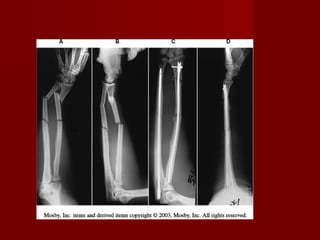

Fractura-luxación del tercio distal del

radio con luxación de la articulación

radio-cubital distal(fractura-luxacion de

Galeazzi)

   La fractura inevitable.

   El tratamiento mediante

reducción      cerrada  e

inmovilización con yeso

tiene una alta taza de

fracaso.

   La reducción abierta y

fijación con placa de

compresión 3.5 es el

método de elección.

   Si aún después de fijar el

radio, la luxación radio

cubital es inestable, se

debe fijar con pines

Kirschner.